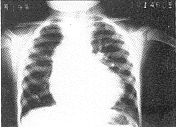

6例X线平片表现为两侧肺血增多,肺门血管扩张,其中有2例肺门呈“残根状”,为右肺动脉受累并重度肺动脉高压。3例表现左侧肺血增多,右侧肺血减少,为左肺动脉受累合并Fallot四联症患者(图1)。5例心脏外形呈二尖瓣型,双侧心室增大,4例呈靴型,右心室增大,主动脉结均有增宽。9例病人心血管造影检查均明确诊断。右心室造影显示主肺动脉显影后仅见1支肺动脉(左或右)显影,患侧肺动脉呈盲端(图2),有6例表现健侧肺动脉明显扩张,主动脉充盈后见另侧肺动脉显影,9例患侧肺动脉均起自升主动脉后壁(图3,4)。

图1 心脏远达片:左肺动脉异常起源合并Fallot四联症,左侧肺血增多,右侧肺血减少

4.影像学诊断及鉴别诊断:本畸形主要依靠影像学诊断,X线平片显示两侧肺血增多,并右肺动脉高压征象,左或(和)右心室增大,似有大量左向右分流畸形,常难以作出正确诊断。但左侧肺动脉受累合并Fallot四联症的病人,左肺接受主动脉高压血流灌注,而右肺由于肺动脉或(和)右室流出道狭窄,导致右心排血受阻,使右肺动脉血流减少,X线平片可出现左侧肺血增多,右侧肺血减少征象,此征象有助于该畸形的平片诊断,本组有3例。多普勒超声心动图检查对本症有一定限度,易漏诊[1]。本组6例漏诊。CT、MRI检查均有助于该症的诊断,但费用偏高。笔者认为心血管造影仍是目前诊断本症的最好方法,可以明确显示解剖及并存畸形,方法应选择右心室及升主动脉造影,正、侧位或加角度投照。